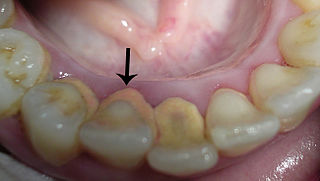

Tandsteen is een verharde laag tandplak die bestaat uit een mineralenlaag. Het speeksel in de mond is rijk aan calcium en fosfaat, dat kan neerslaan op de tanden. Deze zouten reageren met de aanwezige tandplaque en hierdoor ontstaat tandsteen. Een hoge pH-waarde in de mond leidt tot snellere vorming van tandsteen, terwijl gaatjes juist worden veroorzaakt door een lage pH-waarde. Tandsteen is poreuzer dan tandglazuur, waardoor het gemakkelijker verkleurt. Tandsteen boven het tandvlees uit zich meestal als een gele of bruine kleur op de tanden en kiezen. Tandsteen kan ook op of onder de tandvleesrand gaan zitten waardoor het tandvlees geïrriteerd kan raken. Dit veroorzaakt gingivitis. Verharding van tandplaque in tandsteen, kan snel gebeuren, indien de tandplaque niet optimaal verwijderd wordt (zelfs al na 4 dagen na een gebitsreiniging). De meest voorkomende plekken hiervoor zijn bij de uitmondingen van de grote speekselklieren zoals de ondertongse- en de oorspeekselklieren. De tandsteenvorming ontstaat dan aan de binnenkant van de ondertanden en aan de wangzijde van de bovenkiezen.